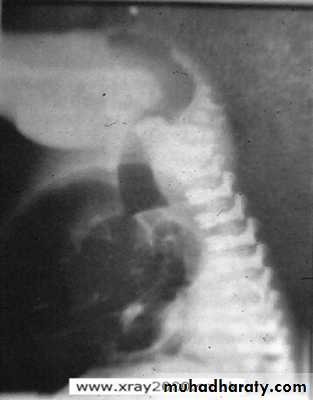

• Signs of low atresia :

• 1- Multiple air fluid level due to obstruction .

• 2- In AP view the distance between the terminal rectal segment and the marker should not exceed 2 cm.

• 3- In lateral view the terminal air shadow is seen above the pubo-coccygeal line.

• Signs of high atresia

• 1- In AP view the distance more than 2 cm .• 2-In lateral view the terminal air is below the pubo-coccygeal line .

Low type

High type